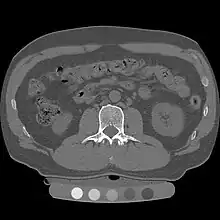

Quantitative computed tomography (QCT) is a medical technique that measures bone mineral density (BMD) using a standard X-ray computed tomography (CT) scanner with a calibration standard to convert Hounsfield units (HU) of the CT image to bone mineral density values.[1] Quantitative CT scans are primarily used to evaluate bone mineral density at the lumbar spine and hip.

In general, solid phantoms placed in a pad under the patient during CT image acquisition are used for calibration. These phantoms contain materials that represent a number of different equivalent bone mineral densities. Usually either calcium hydroxyapatite (CaHAP) or potassium phosphate (K2HPO4) are used as the reference standard.[2]

Originally, conventional 2D QCT used individual, thick CT slice images through each of multiple vertebrae which involved tilting the CT scanner gantry to align the slice with each vertebra. Today, modern 3D QCT uses the ability of CT scanners to rapidly acquire multiple slices to construct three-dimensional images of the human body. Using 3D imaging substantially reduced image acquisition time, improved reproducibility and enabled QCT bone density analysis of the hip.[1]

QCT scan protocols are low-dose and can limit the amount of radiation exposure to between 200-400μSv for a spine exam[6] This is comparable to a set of mammograms and typically substantially less than a standard CT exam. Using other non-IV contrast abdominal or pelvic scans such as a Virtual Colonography studies, the QCT exam can be performed without requiring any further image acquisition or consequent radiation dose to the patient.[7]

Dual use of CT images

Several studies have shown that bone density may be measured by QCT using CT images that were ordered for other purposes. Using pre-existing images, including CT colonography exams,[14] QCT allows for bone density screening without submitting the patient to any additional radiation exposure. The feasibility of using routine abdominal contrast-enhanced CT scans for the evaluation of bone density by QCT has also been demonstrated.[15]